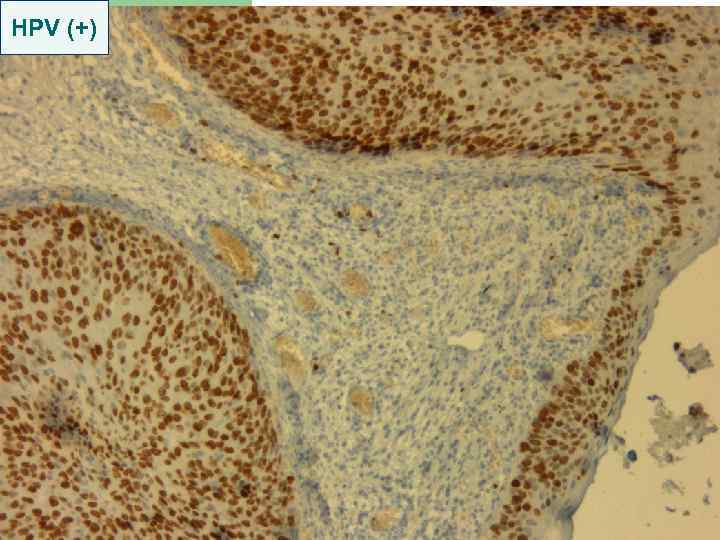

HPV (+)